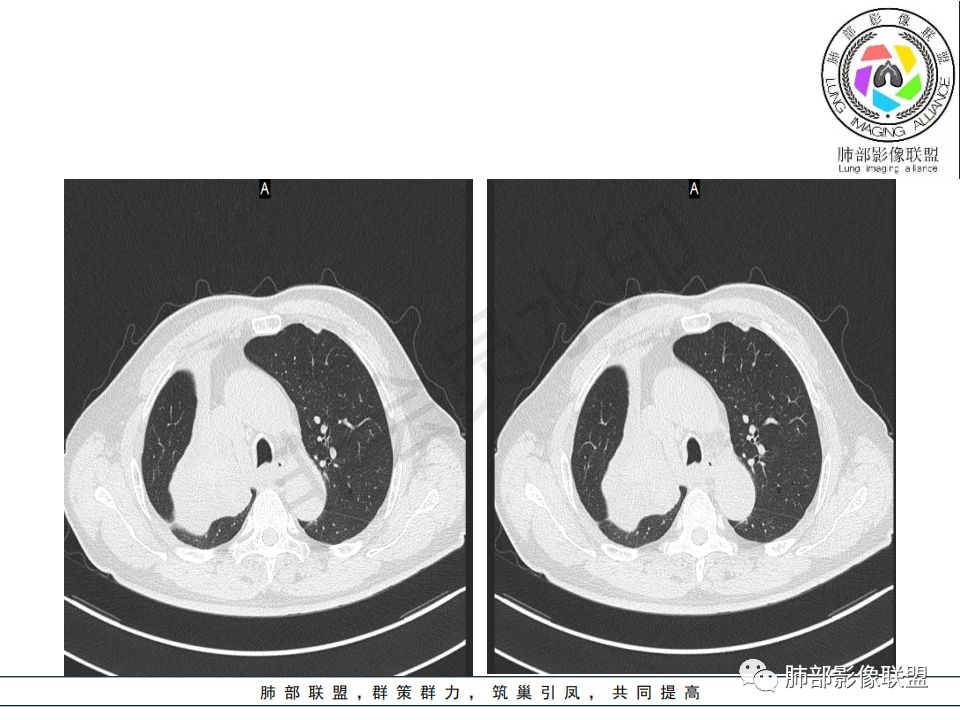

影像:影像右侧大支气管阻塞,临床没有症状或很轻微,要想到胃腺癌转移;胸壁代偿好,透亮度稍低不明显,慢性过程;34.8-52.5HU,主病灶支气管前壁另有1结节,都做成增强两期了,动脉期较平扫有强化;

晨读:患者老年男性,以咳嗽一月就诊,少量白痰,胸CT:纵隔右移,右肺体积缩小,气管下段管壁可见结节样改变,气管软骨变形,气管下段及右主支气管可见新生物向管壁浸润,并向管腔外生长,右上肺肺不张,但不张边缘可见病灶呈膨胀性生长,可见分叶,增强后强化明显。考虑:肺部恶性病变(鳞癌?)

右肺上叶肿块,边缘光滑,略膨隆,近段支气管堵塞,平扫密度均匀,增强后不均匀强化,其内可见不规则血管和坏死,纵隔淋巴结肿大,老年男性,无感染性病史,综合考虑恶性肿瘤(鳞癌,腺癌),鉴别:OP(一般下叶多见)

晨读病例:老年男性,症状轻,右侧胸廓略塌陷,右肺主支气管内外软组织影,支气管变窄截断,右肺上叶不张,其内见细砂样钙化,周围看见小结节,右肺门看见一淋巴结稍大,增强不均匀强化,胃癌病史,常规考虑:转移,或原发肺恶性鳞癌。鉴别支气管TB?

从强化情况和冠状位看主要还是从外向内的一个肿块,有不张,但不张范围不大,近端支气管堵塞,考虑腺癌或类癌(原发或转移都可能),鉴别鳞癌。

@曹坤,河北保定清苑区人民医院ct室 肿块大,阻塞和不张范围小,强化这么大肿块没有明显坏死,鳞癌这样相对少见了

@刘鋆(福州长乐区医院)影像科 转移啊,腔外都在生长,部分通过支气管壁进入腔内

@刘鋆(福州长乐区医院)影像科 先转移生长到外面,然后进入腔内生长,也是外朝内一种,与平时那种外朝内生长逐渐侵犯近端气管没有太多区别,只不过这个是转移而已。

1.右肺上叶较大块影,密度不均,轻度强化并见低密度区,所属支气管截断并腔内突入,是符合肺鳞癌的影像学特征和生物学行为的。